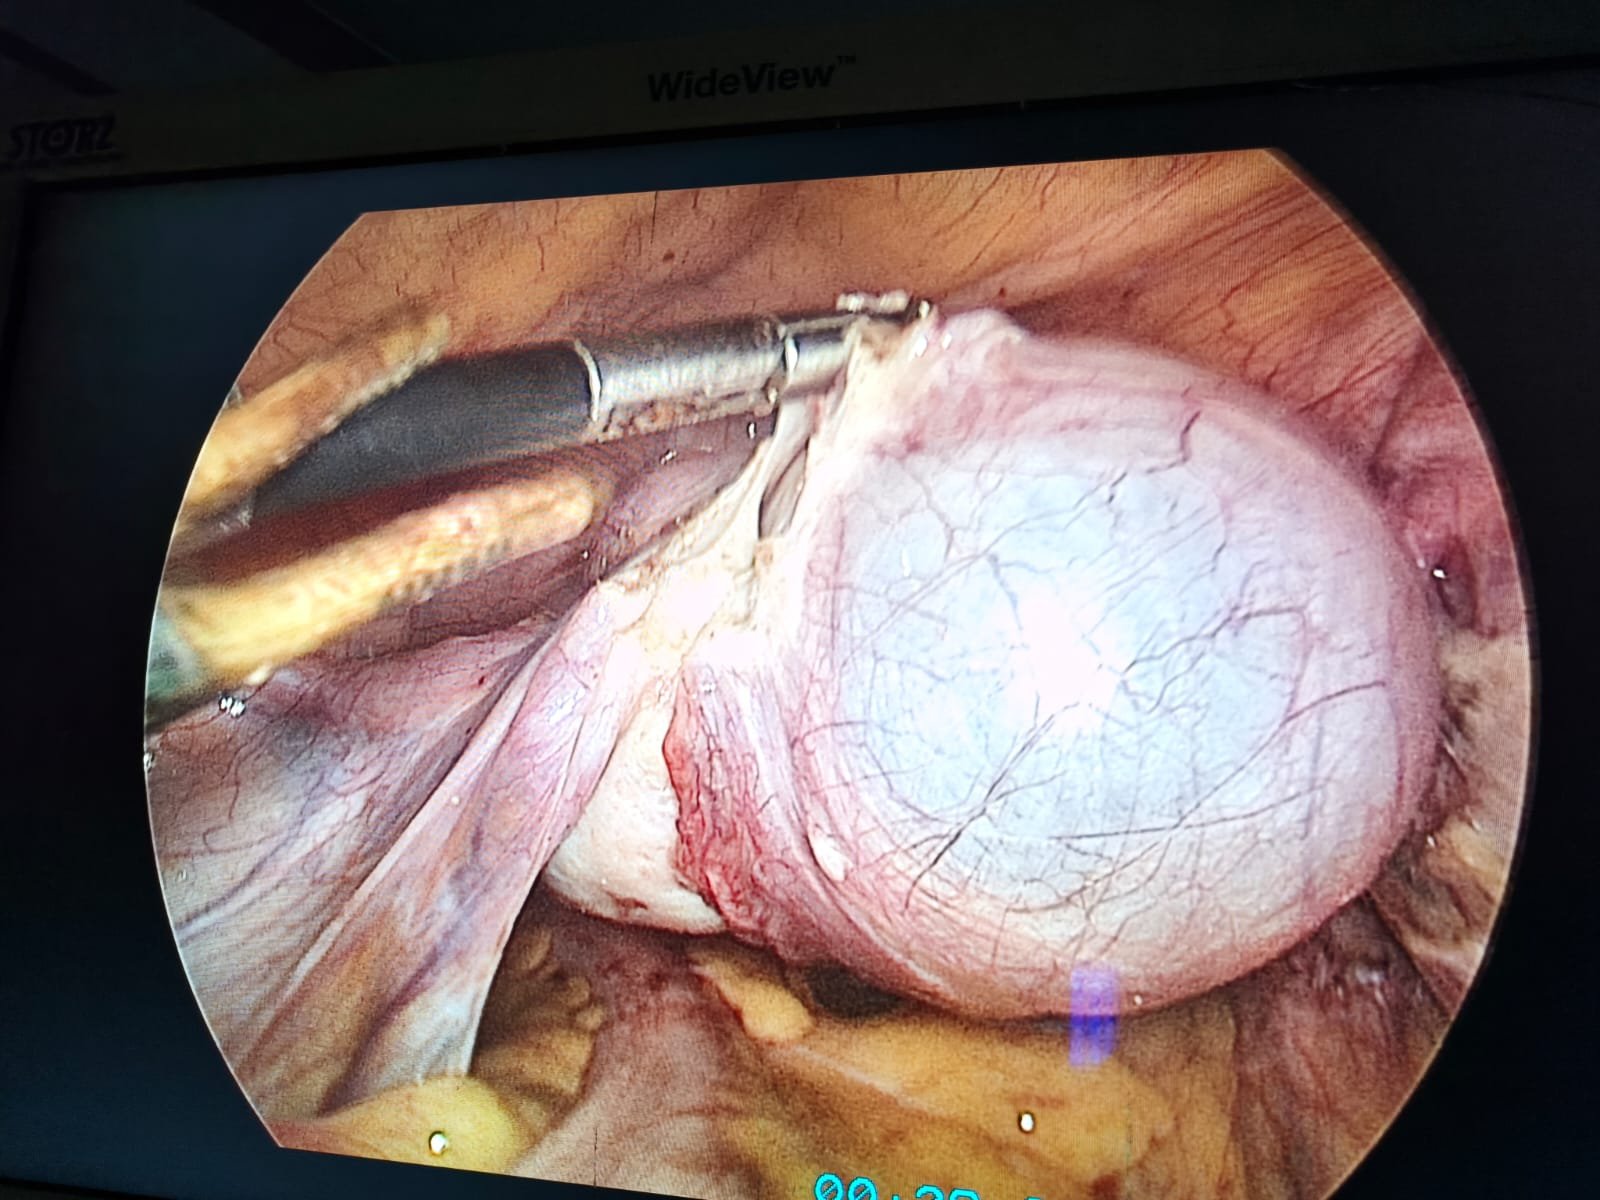

▶ Laproscopic gynaecology surgery

Rana Hospital offers advanced care in Maternity, Gynecology, ENT, and Cancer Surgery. Our expert doctors provide personalized treatment with modern technology. We are committed to your family’s health, comfort, and speedy recovery.